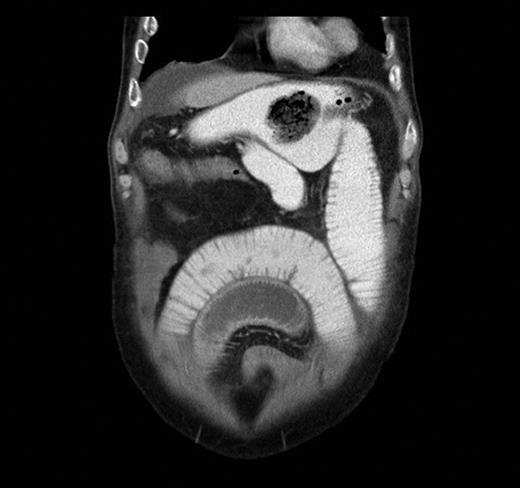

A contrast-enhanced CT scan was arranged and it showed features of SBO with collapse of the terminal ileum. There was evidence of a previous gastrojejunostomy with suspected foreign bodies in the stomach and proximal ileum. (Figs 1 and 2) .

Contrast-enhanced abdominal CT scan in coronal view showing evidence of gastrojejunostomy and visible foreign body in the stomach and features of small bowel obstruction.